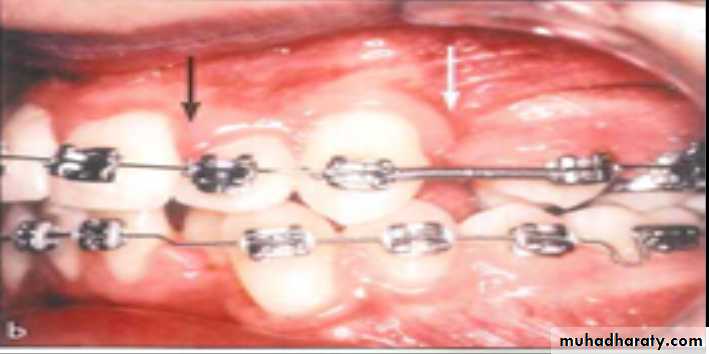

Bacterial plaque at the gingival margin is the initiating and most significant factor in gingival inflammation. Patients undergoing orthodontic treatment have increased retention sites for microbial samples, which may be responsible for gingivitis.Higher plaque indices ,bleeding tendencies and pocket depths have been observed for molars with orthodontic bands than for bonded brackets.

Loss of attachment was also more common for molars with orthodontic bands which can be due to the difficulty in plaque removal on the gingival margin of the bands or due to mechanical injury caused by the placement of the band too deep within the gingival pocket.

Orthodontic closure of extraction sites often results in compressed gingival tissue with an interdental fold most frequently at the buccal aspect of the maxillary first molar extraction site or at the mandibular first molar extraction site

A proper oral hygiene regimen in patients with fixed orthodontic appliances (especially around molar band) prevent plaque accumulation, bleeding tendency, and loss of attachment. The use of light forces in closing extraction space will minimize compression of the gingival tissue with interdental folds, which may be responsible for relapse after closure of the gap.